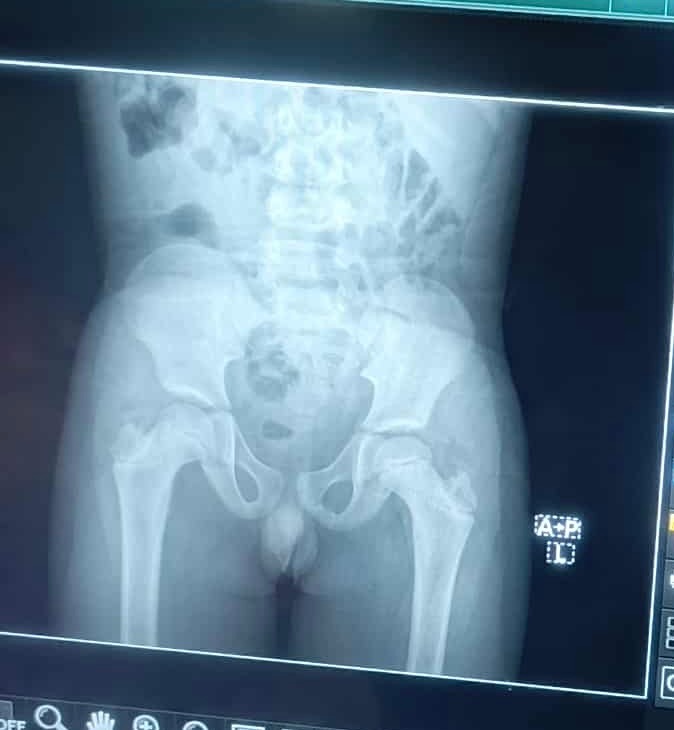

Hi to all my family and friends, I have started a fundraising page to help my 10-year-old nephew in Liberia who is hospitalized from a fall. He has injuries that have him in so much pain. From what I see from the X-ray, it looks like his spine and hips were moved. My sister took him to the hospital, but they are refusing to treat him without money. They were able to do an X-ray with the little money I had, but they can't do anything else without payment upfront. It's heartbreaking as a mother of 5 to watch my nephew sit in the hospital's uncomfortable bed, crying and screaming in pain with no treatment as his voice echoes through the building. Please help him; even a prayer or anything will be helpful. Please, I can't imagine losing another family member.

Update: I had to change the amount because my nephew needs surgery as his spine is broken his belly is swollen and he can’t feel his lower body. We have to transfer him to a better hospital that can help him with the surgery, but it’s expensive they won’t help him with out the money. Please family and friends I appreciate everything as I’m in tears right now I don’t know how to thank you let god bless you for your help and support.